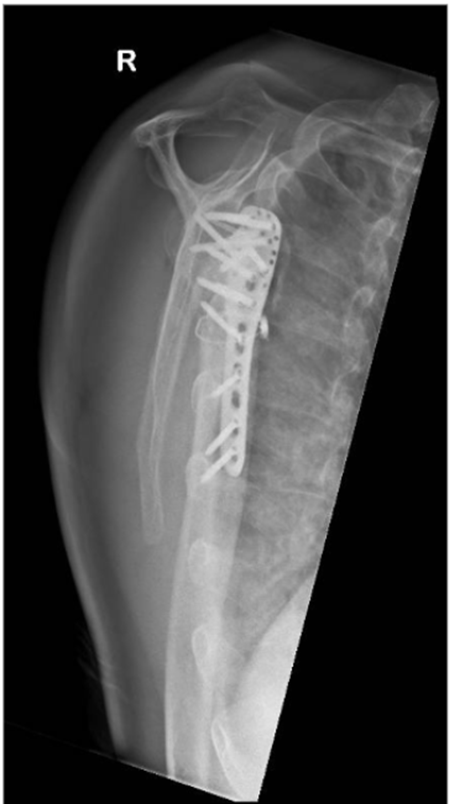

The patient underwent open reduction internal fixation (ORIF) on post-injury day 11. Following a deltopectoral approach and biceps tenodesis, the 4-part PHFD was seen. The humeral head was posteriorly dislocated and impacted upon the posterior glenoid with a nondisplaced head split. The greater tuberosity fragment was identified with an intact supraspinatus However there was an avulsion of the subscapularis off the lesser tuberosity. The humeral head was reduced with judicious soft tissue management and assessed in-situ to prevent secondary injury and ischemia. The articular block was secured with 2 headless compression screws. The neck-shaft angle was restored using plate-assisted reduction and an angular stable construct was achieved with an anatomical locking compression plate (Synthes PHILOSTM). To prevent varus malunion, the height of the plate was determined on fluoroscopy (Image 2) to enable the inferomedial ‘kickstand’ screw [31]. The medial calcar was reduced and cerclaged to the plate for bony apposition and increased fixation strength. Cement augmentation (Stryker Hydroset) was performed. Transosseous repair of the Subscapularis was done with closure of the rotator interval.

Image 2: Intraoperative fluoroscopy demonstrating satisfactory anatomical reduction of the 4-part proximal humeral posterior fracture-dislocation.

Image 3: Immediate postoperative radiographs of the right shoulder.

A. Anteroposterior (AP) view

B. Valpeau view

C. Lateral/ Y scapula view